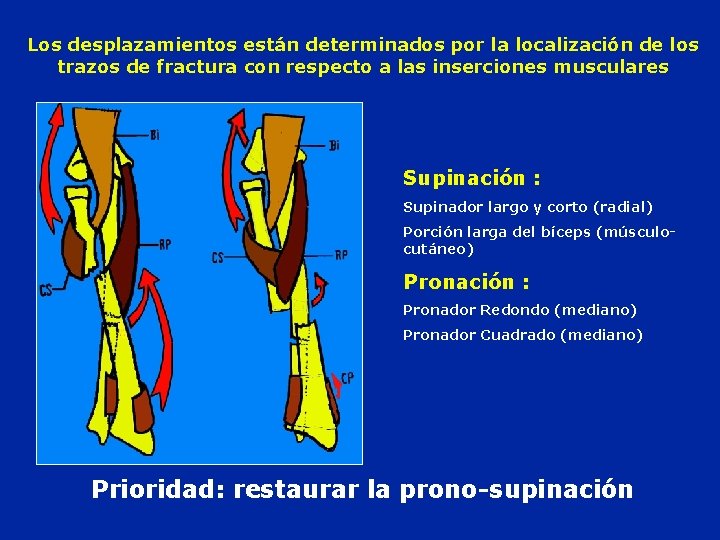

Los desplazamientos están determinados por la localización de los trazos de fractura con respecto a las inserciones musculares Supinación : Supinador largo y corto (radial) Porción larga del bíceps (músculocutáneo) Pronación : Pronador Redondo (mediano) Pronador Cuadrado (mediano) Prioridad: restaurar la prono-supinación